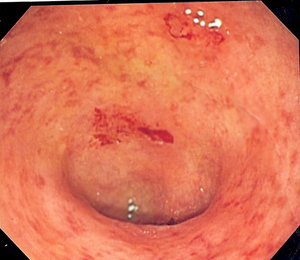

之后,应对患者进行肠内窥镜检查,在肠镜下,对炎症和溃疡的形态以及受到侵犯的肠管区域进行观察。

最后,采取大肠粘膜表面样本,进行病理活检。经过以上诊断步骤,大部分溃疡性大肠炎的患者可以得到确诊。

出现明显溃疡症状的大肠表面,来源:维基百科溃疡性大肠炎条目